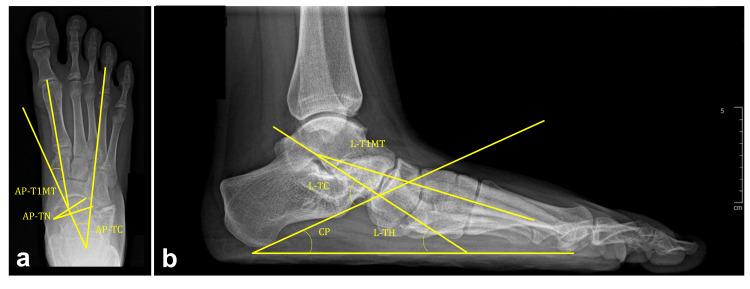

A case-control retrospective study was conducted on 50 patients (80 feet) aged 12.4±2.5 years who underwent CLP. A clinical (demographic parameters, etiology, Gross Motor Function Classification System (GMFCS) level) and radiological evaluation were assessed preoperatively and repeated postoperatively at 56.5±32.5 months. Two methods of osteotomy bone fixation were studied: K-wires vs. eight-plate. Standing anteroposterior (AP) and lateral (L) radiographs were done, and the following radiographic parameters were measured: calcaneocuboid (CC) joint subluxation classified into normal, moderate, and severe (L); AP and L talo-first metatarsal (T1MT) angle; AP talonavicular (TN) coverage angle; AP and L talocalcaneal (TC) angle; calcaneal pitch (CP) angle; and L talo-horizontal (TH) angle. Mosca's criteria were used for clinical and radiological assessments. The association between demographic data, clinical and radiological results, and the variation between preoperative and postoperative angles were studied. The main risk factors affecting clinical results and CC joint subluxation were investigated (logistic regression and analysis of covariance (ANCOVA)).

对50例(80足)年龄在12.4±2.5岁接受CLP手术的患者进行病例对照回顾性研究。术前进行临床(人口统计学参数、病因、粗大运动功能分类系统(GMFCS)水平)和影像学评估,并在术后56.5±32.5个月重复评估。研究了两种截骨内固定方法:克氏针与八孔钢板。拍摄站立位前后位(AP)和侧位(L)X线片,并测量以下影像学参数:跟骰(CC)关节半脱位分为正常、中度和重度(L);AP和L位距骨-第一跖骨(T1MT)角;AP位距舟(TN)覆盖角;AP和L位距跟(TC)角;跟骨倾斜(CP)角;以及L位距骨-水平(TH)角。采用Mosca标准进行临床和影像学评估。研究了人口统计学数据、临床和影像学结果之间的关联,以及术前和术后角度的变化。调查了影响临床结果和CC关节半脱位的主要危险因素(逻辑回归和协方差分析(ANCOVA))。